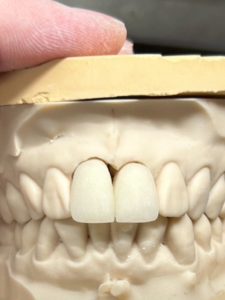

技工士さんと形態の打ち合わせ

私は長めのサイズが好みよ〜ん💜🩷